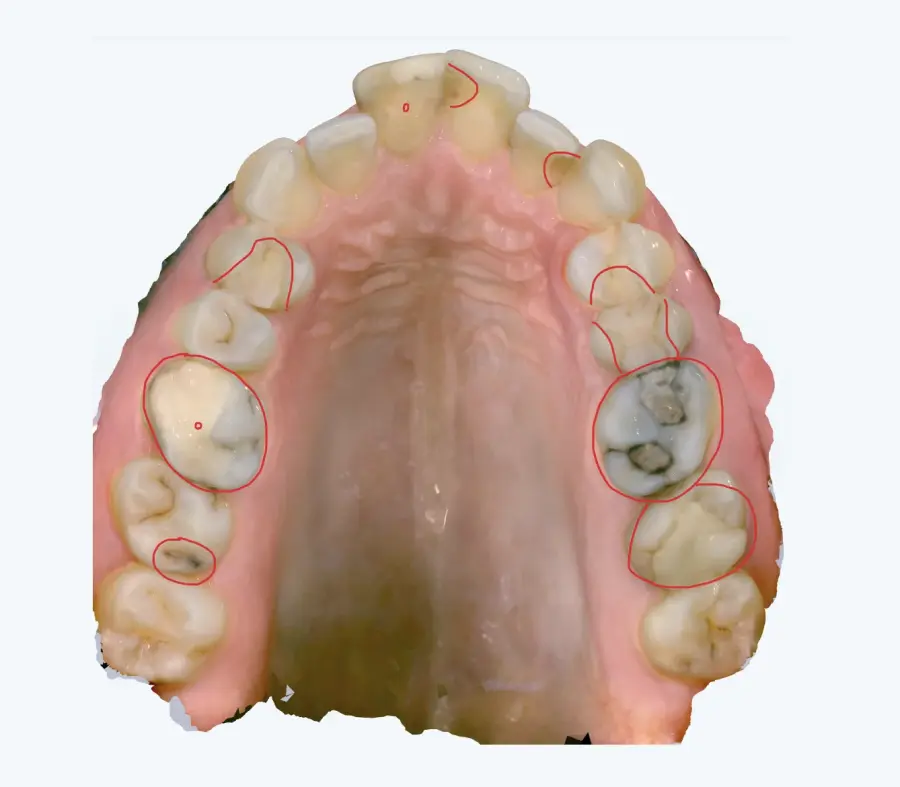

Papildus norādām, ka arī no intraorālās skenēšanas datiem (tostarp ekrānšāviņiem) ir identificējamas vairākas klīniski nozīmīgas problēmas, tai skaitā:

* aktīvi kariozi bojājumi,

* bojātas, lūzušas un plaisājušas plombes,

* vairāku zobu audu apjoma zudums,

* citas strukturālas izmaiņas, kas var ietekmēt turpmāko ortodontisko ārstēšanu.